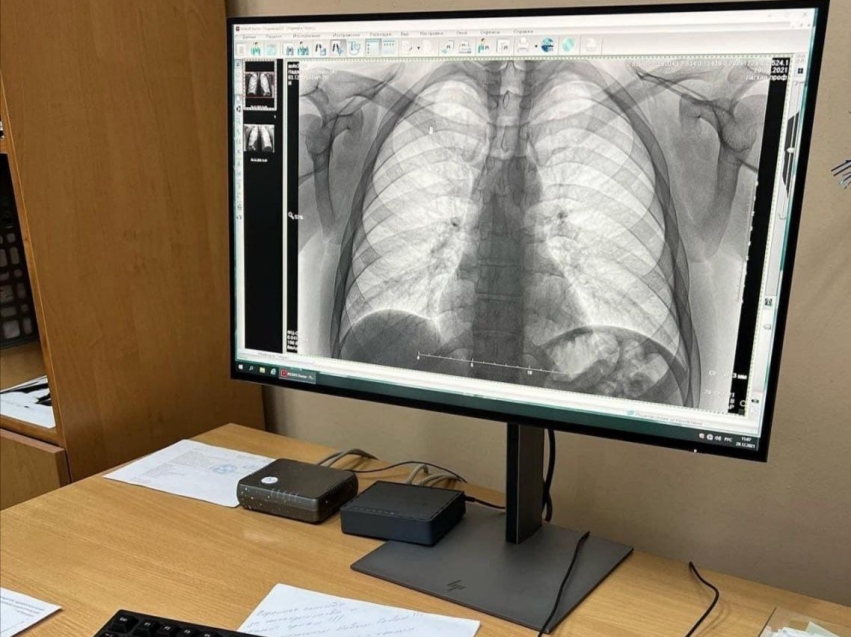

Необходимые тесты сделали все желающие бесплатно в День открытый дверей в краевом фтизиопульмонологическом центре. Пациентам сделали пробы манту, флюорографию и не только.

«Такие мероприятия мы делаем каждый год. В этот раз обследования прошли 120 человек, из них 20 детей. Помимо этого, мы проводим и другие акции. Например, наши волонтеры дарят надувные белые ромашки, как символ чистого дыхания, в центре города и рассказывают о профилактике заболеваний легких. Благодаря этому за прошлый год успешно пролечено около 400 человек», - рассказал руководитель центра Надежда Пикалова.

Напомним, ежегодно для раннего выявления болезни детям нужно ставить манту, а взрослым проходить диспансеризацию и делать флюорографию.